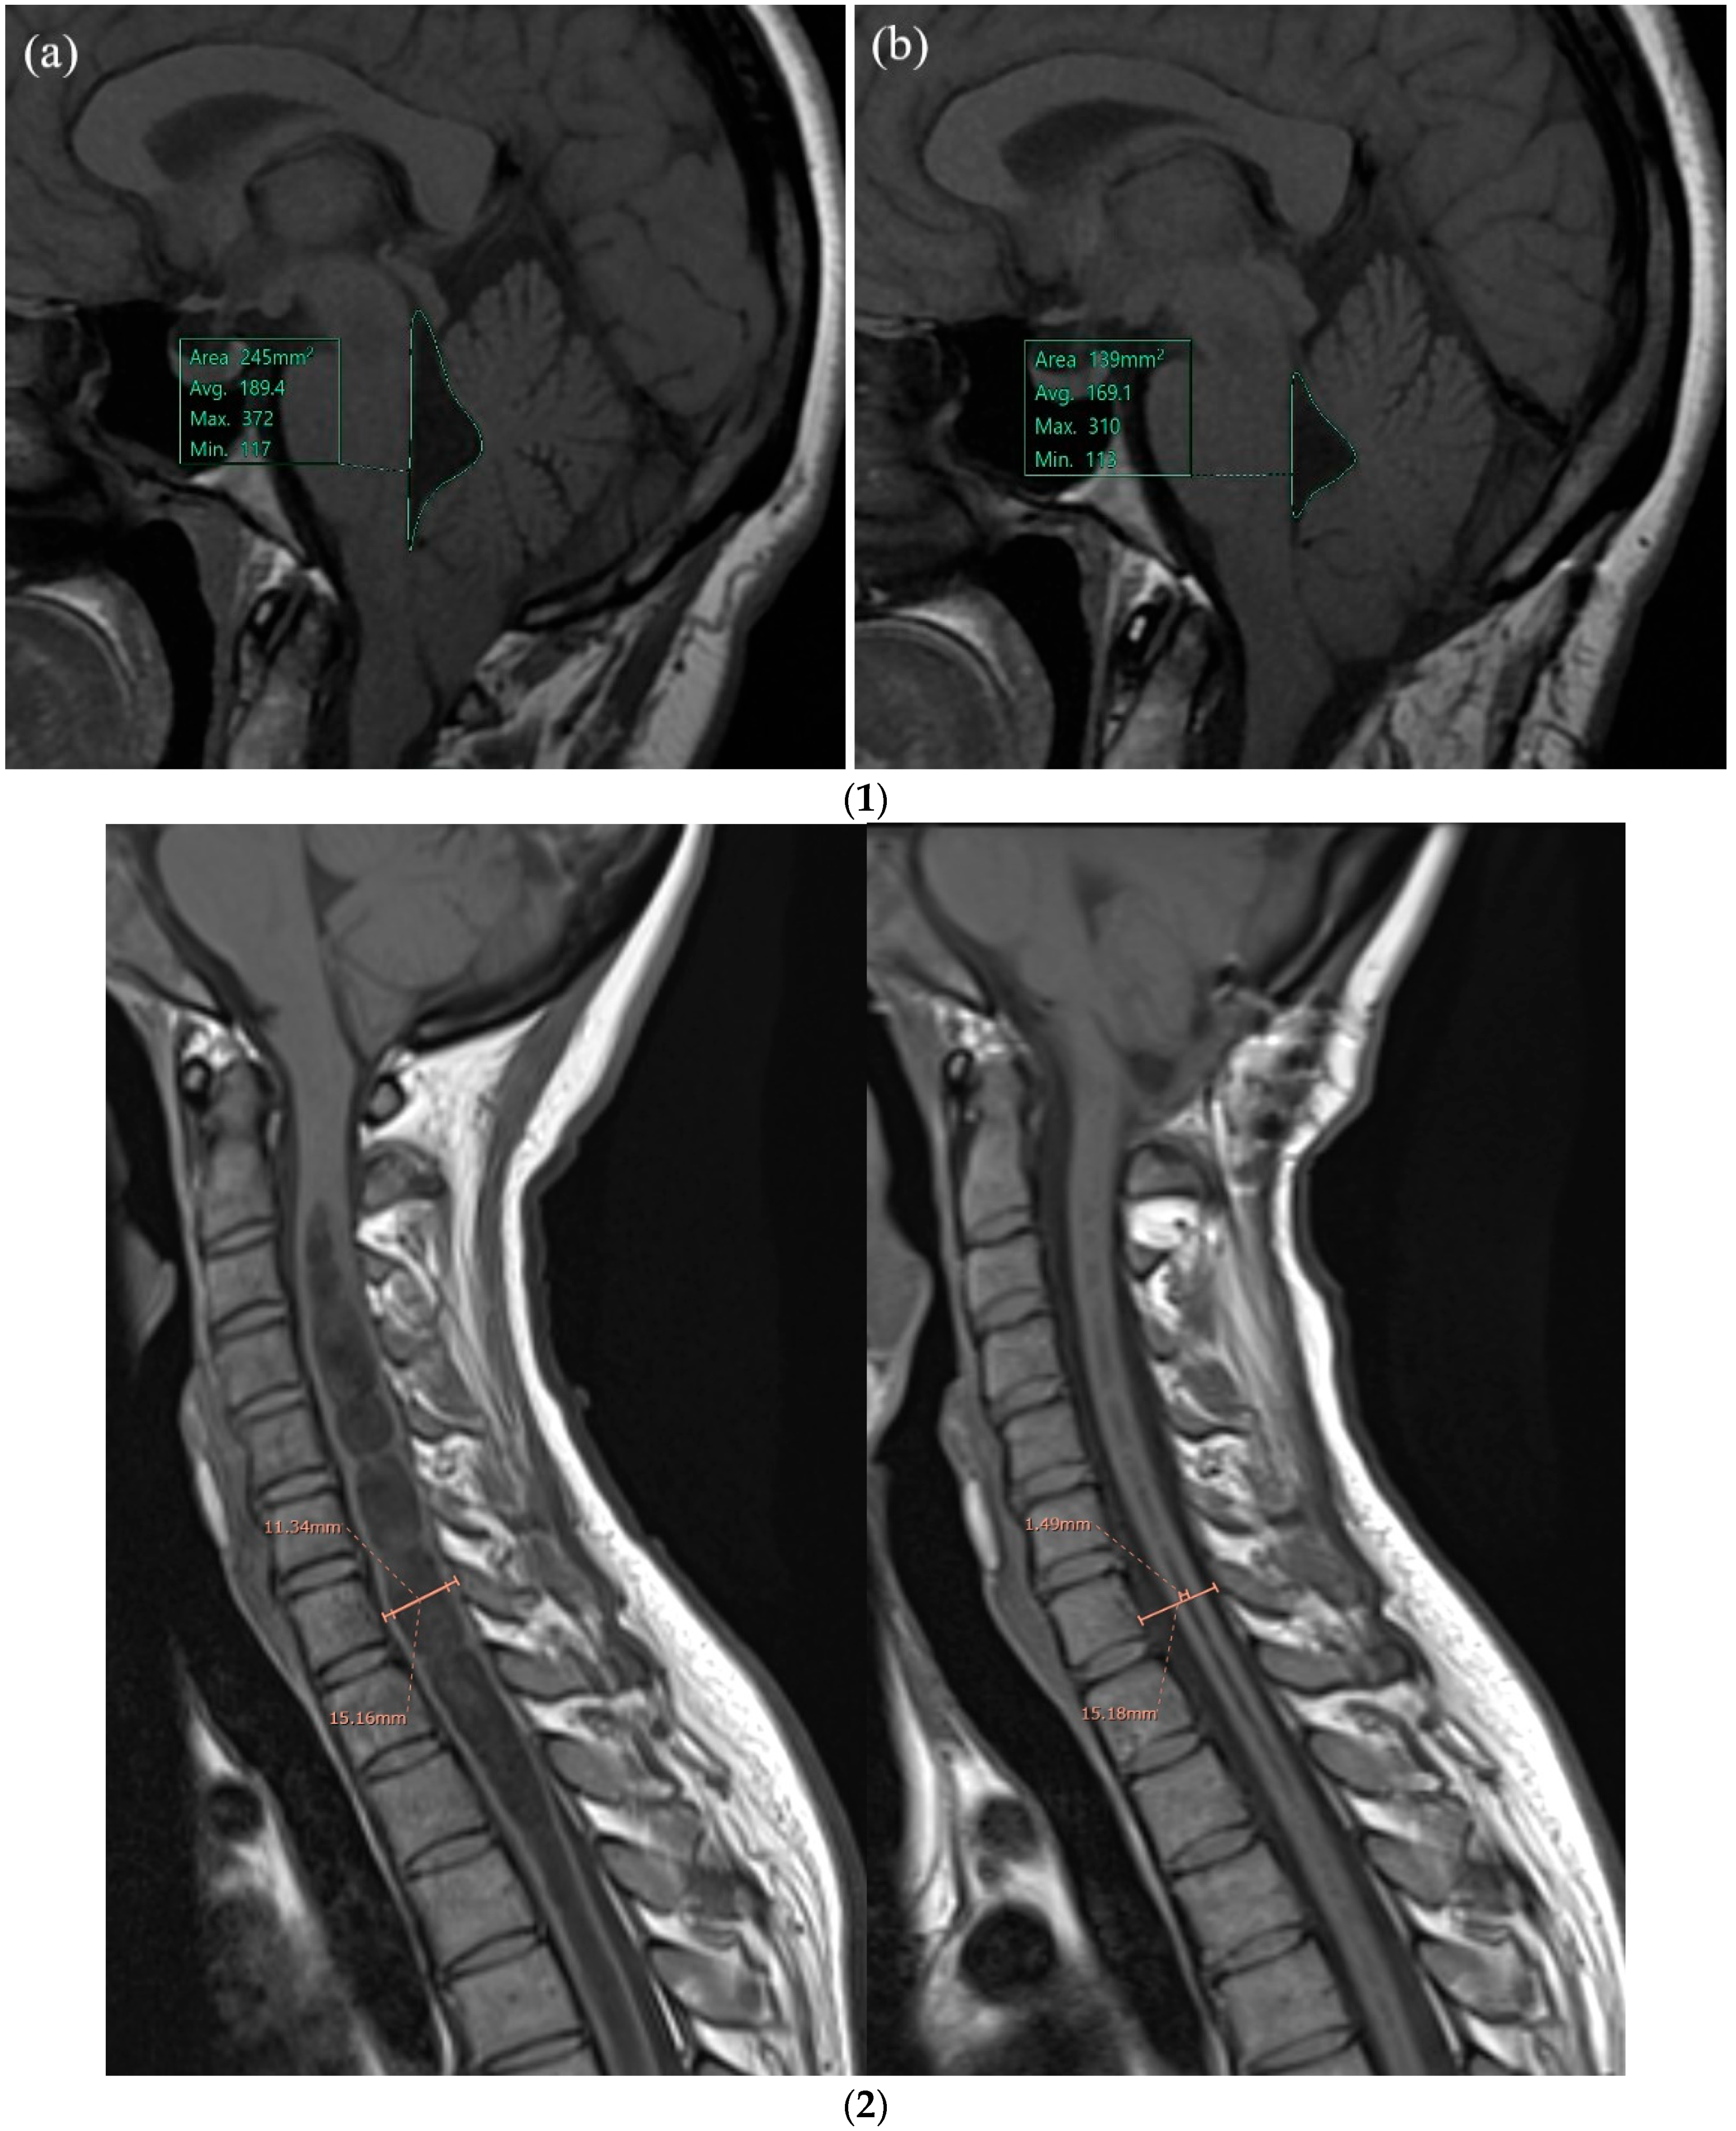

3.1. Fourth Ventricle Area in Patients with CM1 ± Syr versus Normal Controls

| Fourth Ventricle Area (T0) | |||||||||

| All | 36 | 124.23 | 52.63 | 111 | 36 | 98.72 | 24.78 | 98.5 | 0.0438 |

| Syr | 26 | 129.8 | 57.96 | 113 | 36 | 98.72 | 24.78 | 98.5 | 0.0328 |

| CM1 | 10 | 110.3 | 34.71 | 105.5 | 36 | 98.72 | 24.78 | 98.5 | 0.3866 |

| Fourth Ventricle Area (Tlast) | |||||||||

| All | 32 | 110.62 | 40.27 | 99.5 | 36 | 98.72 | 24.78 | 98.5 | 0.3382 |

| Syr | 22 | 116.72 | 42.92 | 103.5 | 36 | 98.72 | 24.78 | 98.5 | 0.1546 |

| CM1 | 10 | 97.2 | 31.5 | 90.5 | 36 | 98.72 | 24.78 | 98.5 | 0.7709 |